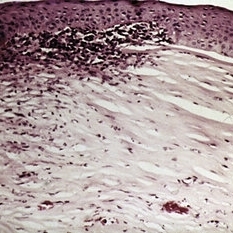

Slide 12-24

Feb 27 2019 by Lancaster Course in Ophthalmology

Sequelae. Basal layer of the corneal epithelium is pale and swollen by edema fluid. Further accumulation of edema fluid will lift the epithelium off of Bowman's membrane, resulting in bullous keratopathy (see Slide 12-16) (Masson's tri chromex250).

Condition/keywords: edema, epithelium, sequelae